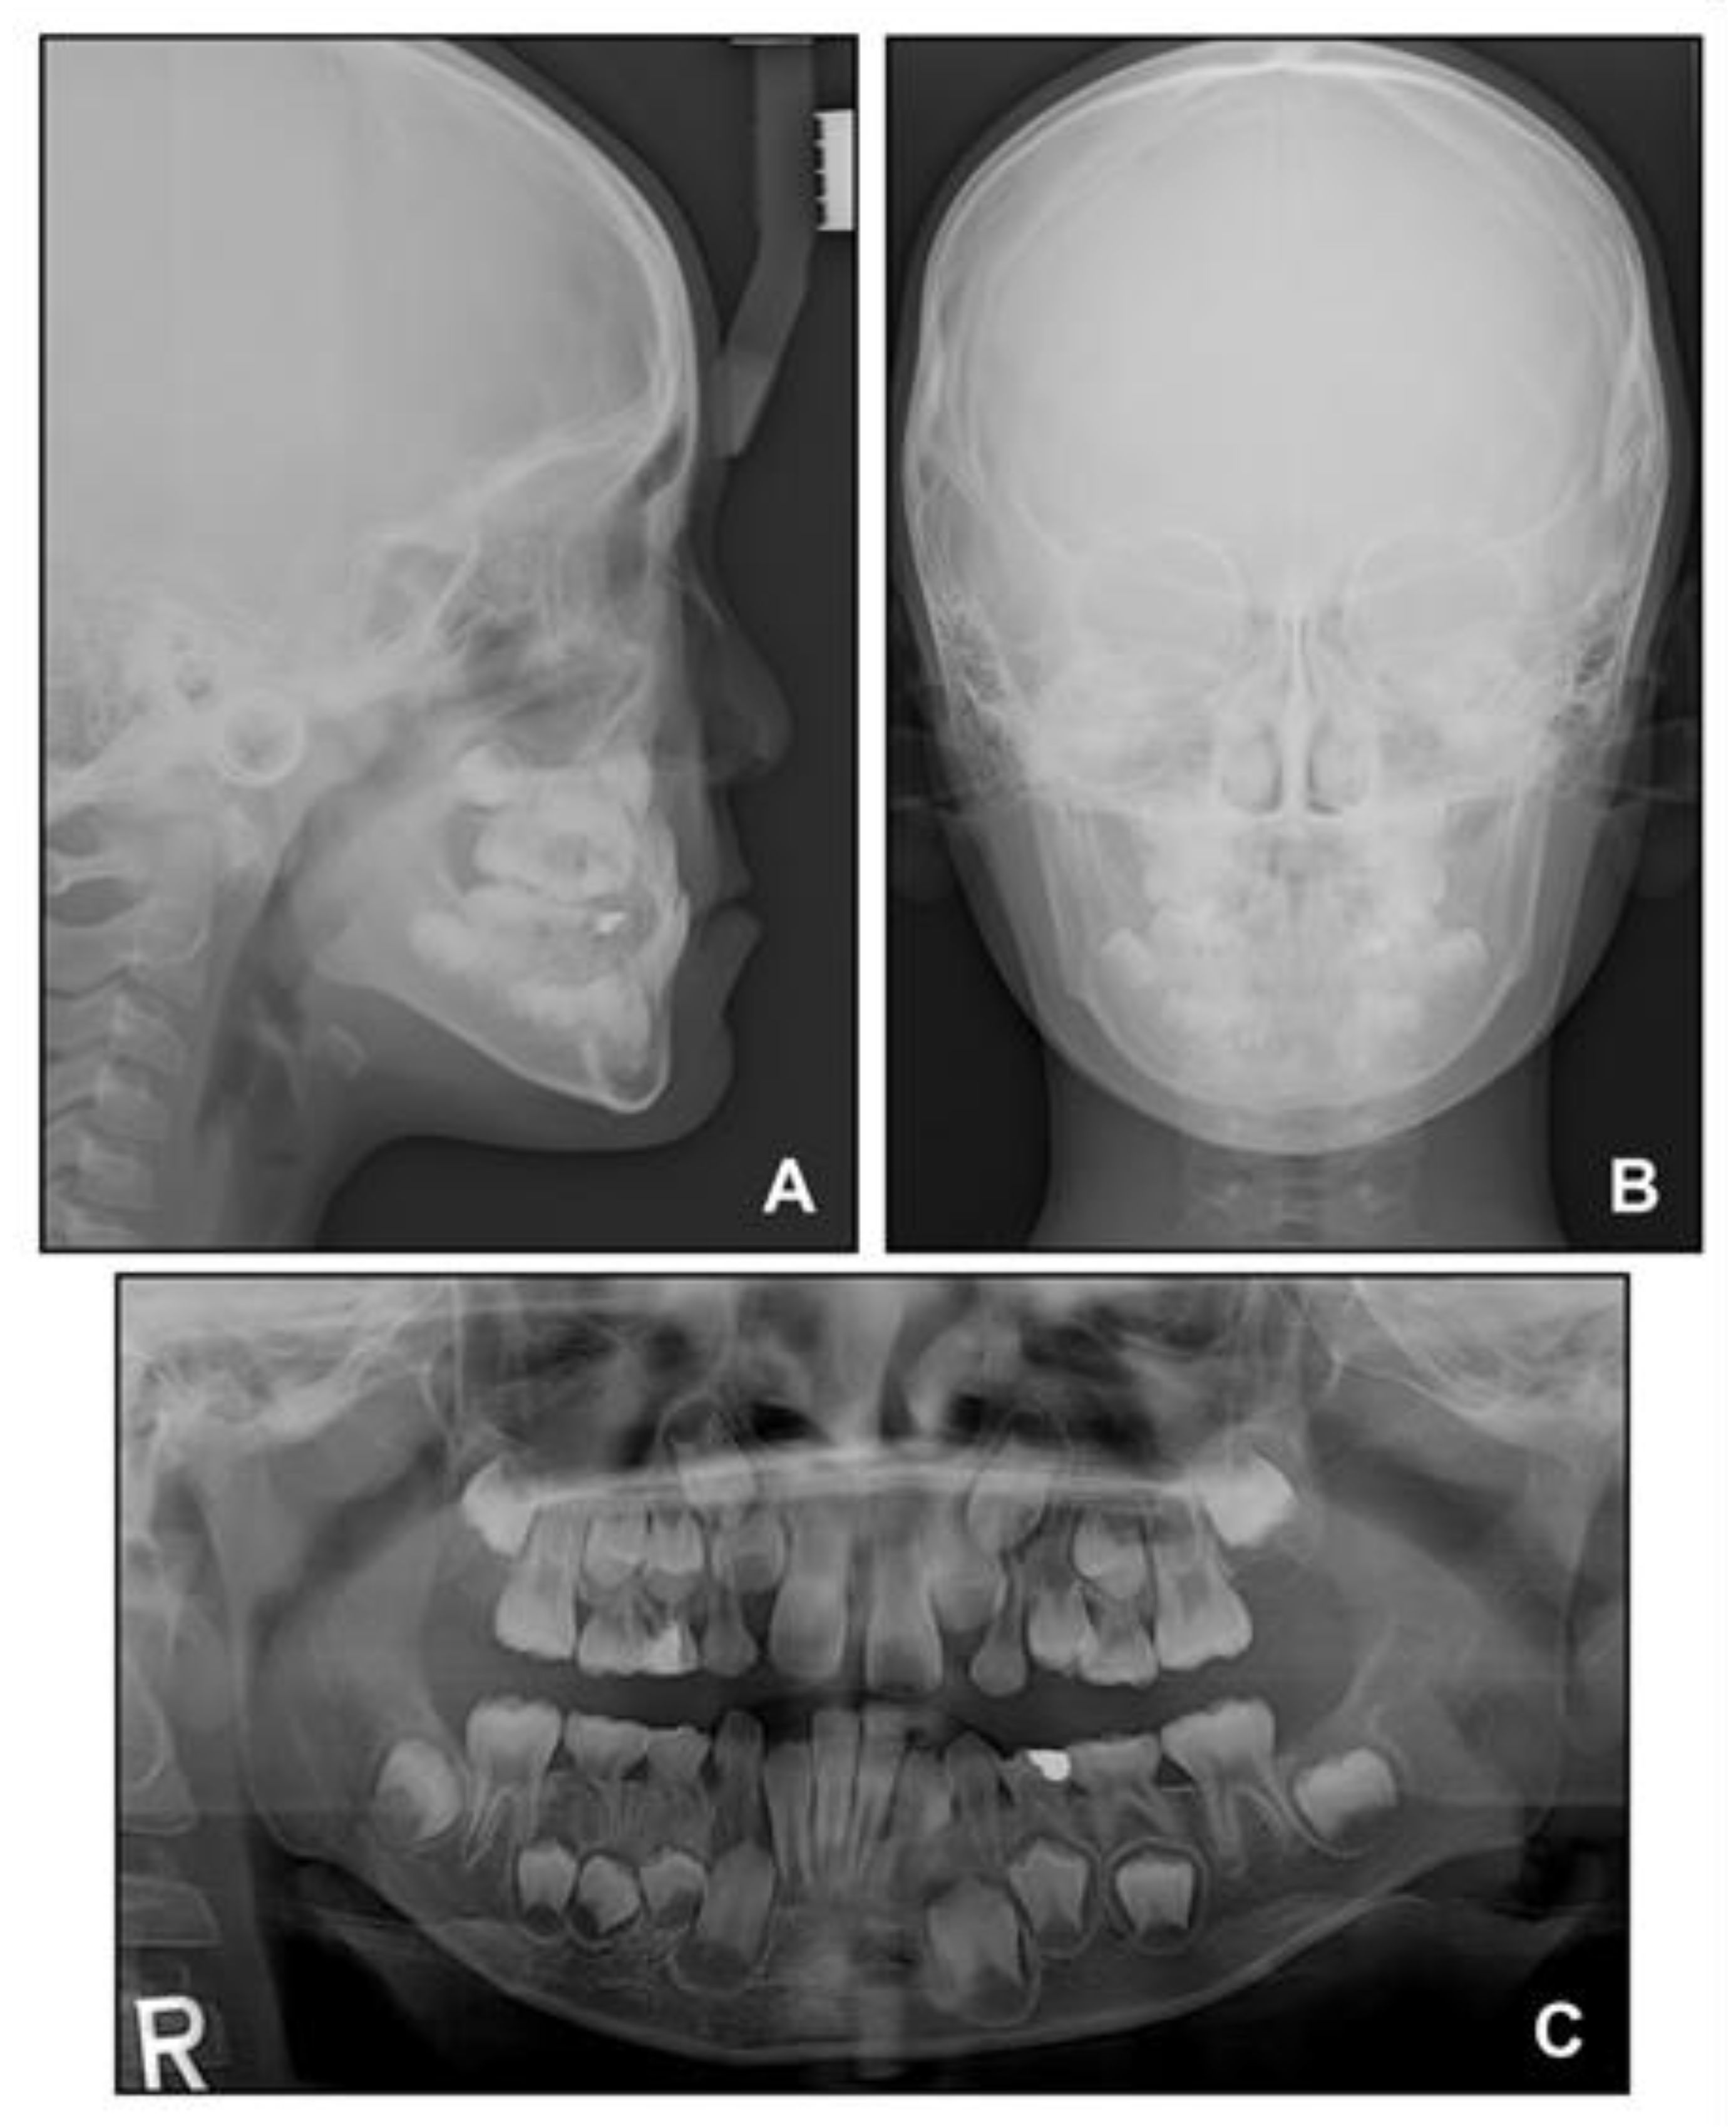

Lateral cephalometric analysis showed an angle of the lines connecting the sella, nasion, and point A (SNA) of 75.4°, an angle of the lines connecting the sella, nasion, and point B (SNB) of 75.7°, and angle of the lines connecting point A, nasion, and point B (ANB) of −0.3° (Table 1 and Figure 3). Both maxillary and mandibular incisors were lingually inclined, and the upper lip was retruded with respect to the Ricketts’ esthetic line. In posteroanterior cephalometric analysis, there were no noticeable asymmetric features. A panoramic radiograph showed that a supernumerary tooth was impacted in the right mandibular premolar area. There were no pathologic osseous findings in the gingival hypertrophic area of the anterior mandible.

Figure 3. Pre-treatment radiographs: (A) Lateral cephalogram; (B) Posteroanterior cephalogram; (C) Panoramic radiograph.